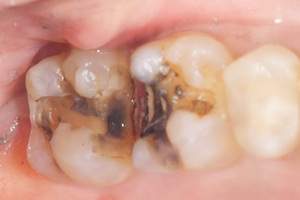

経年劣化していた銀歯

麻布十番歯科で銀歯の症例の口腔内写真